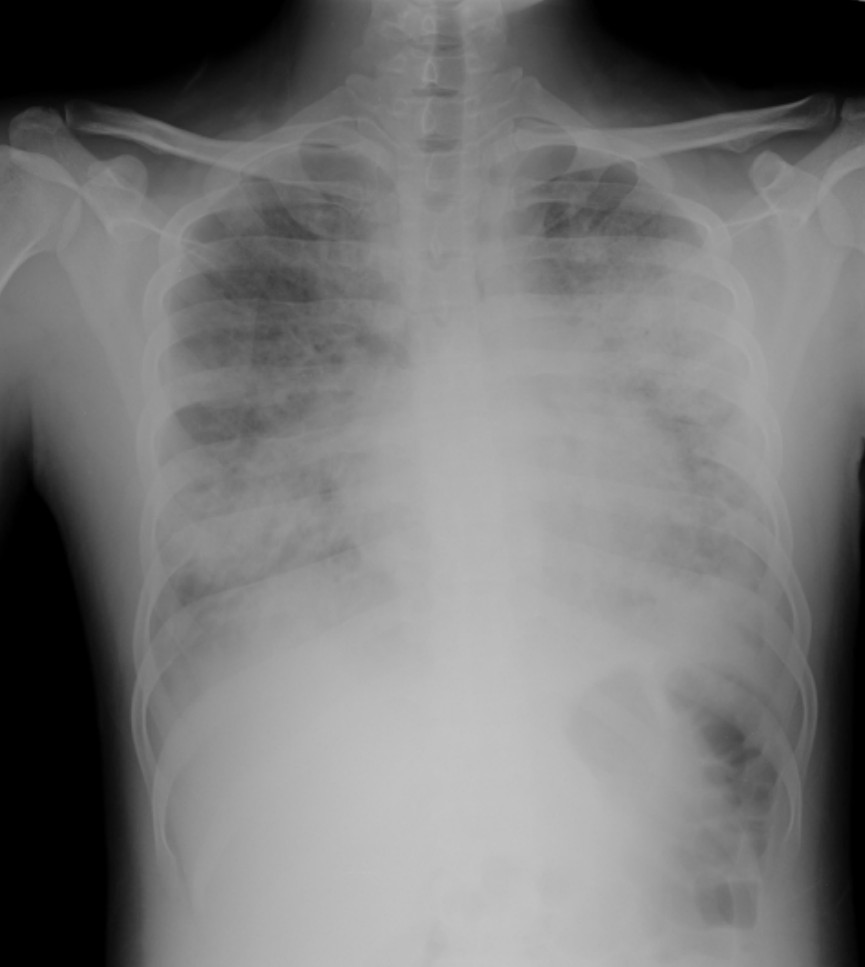

Severe pneumonia in infant

An 11-month-old girl is brought into your rural emergency department with suspected community acquired pneumonia after being unwell for 5 …